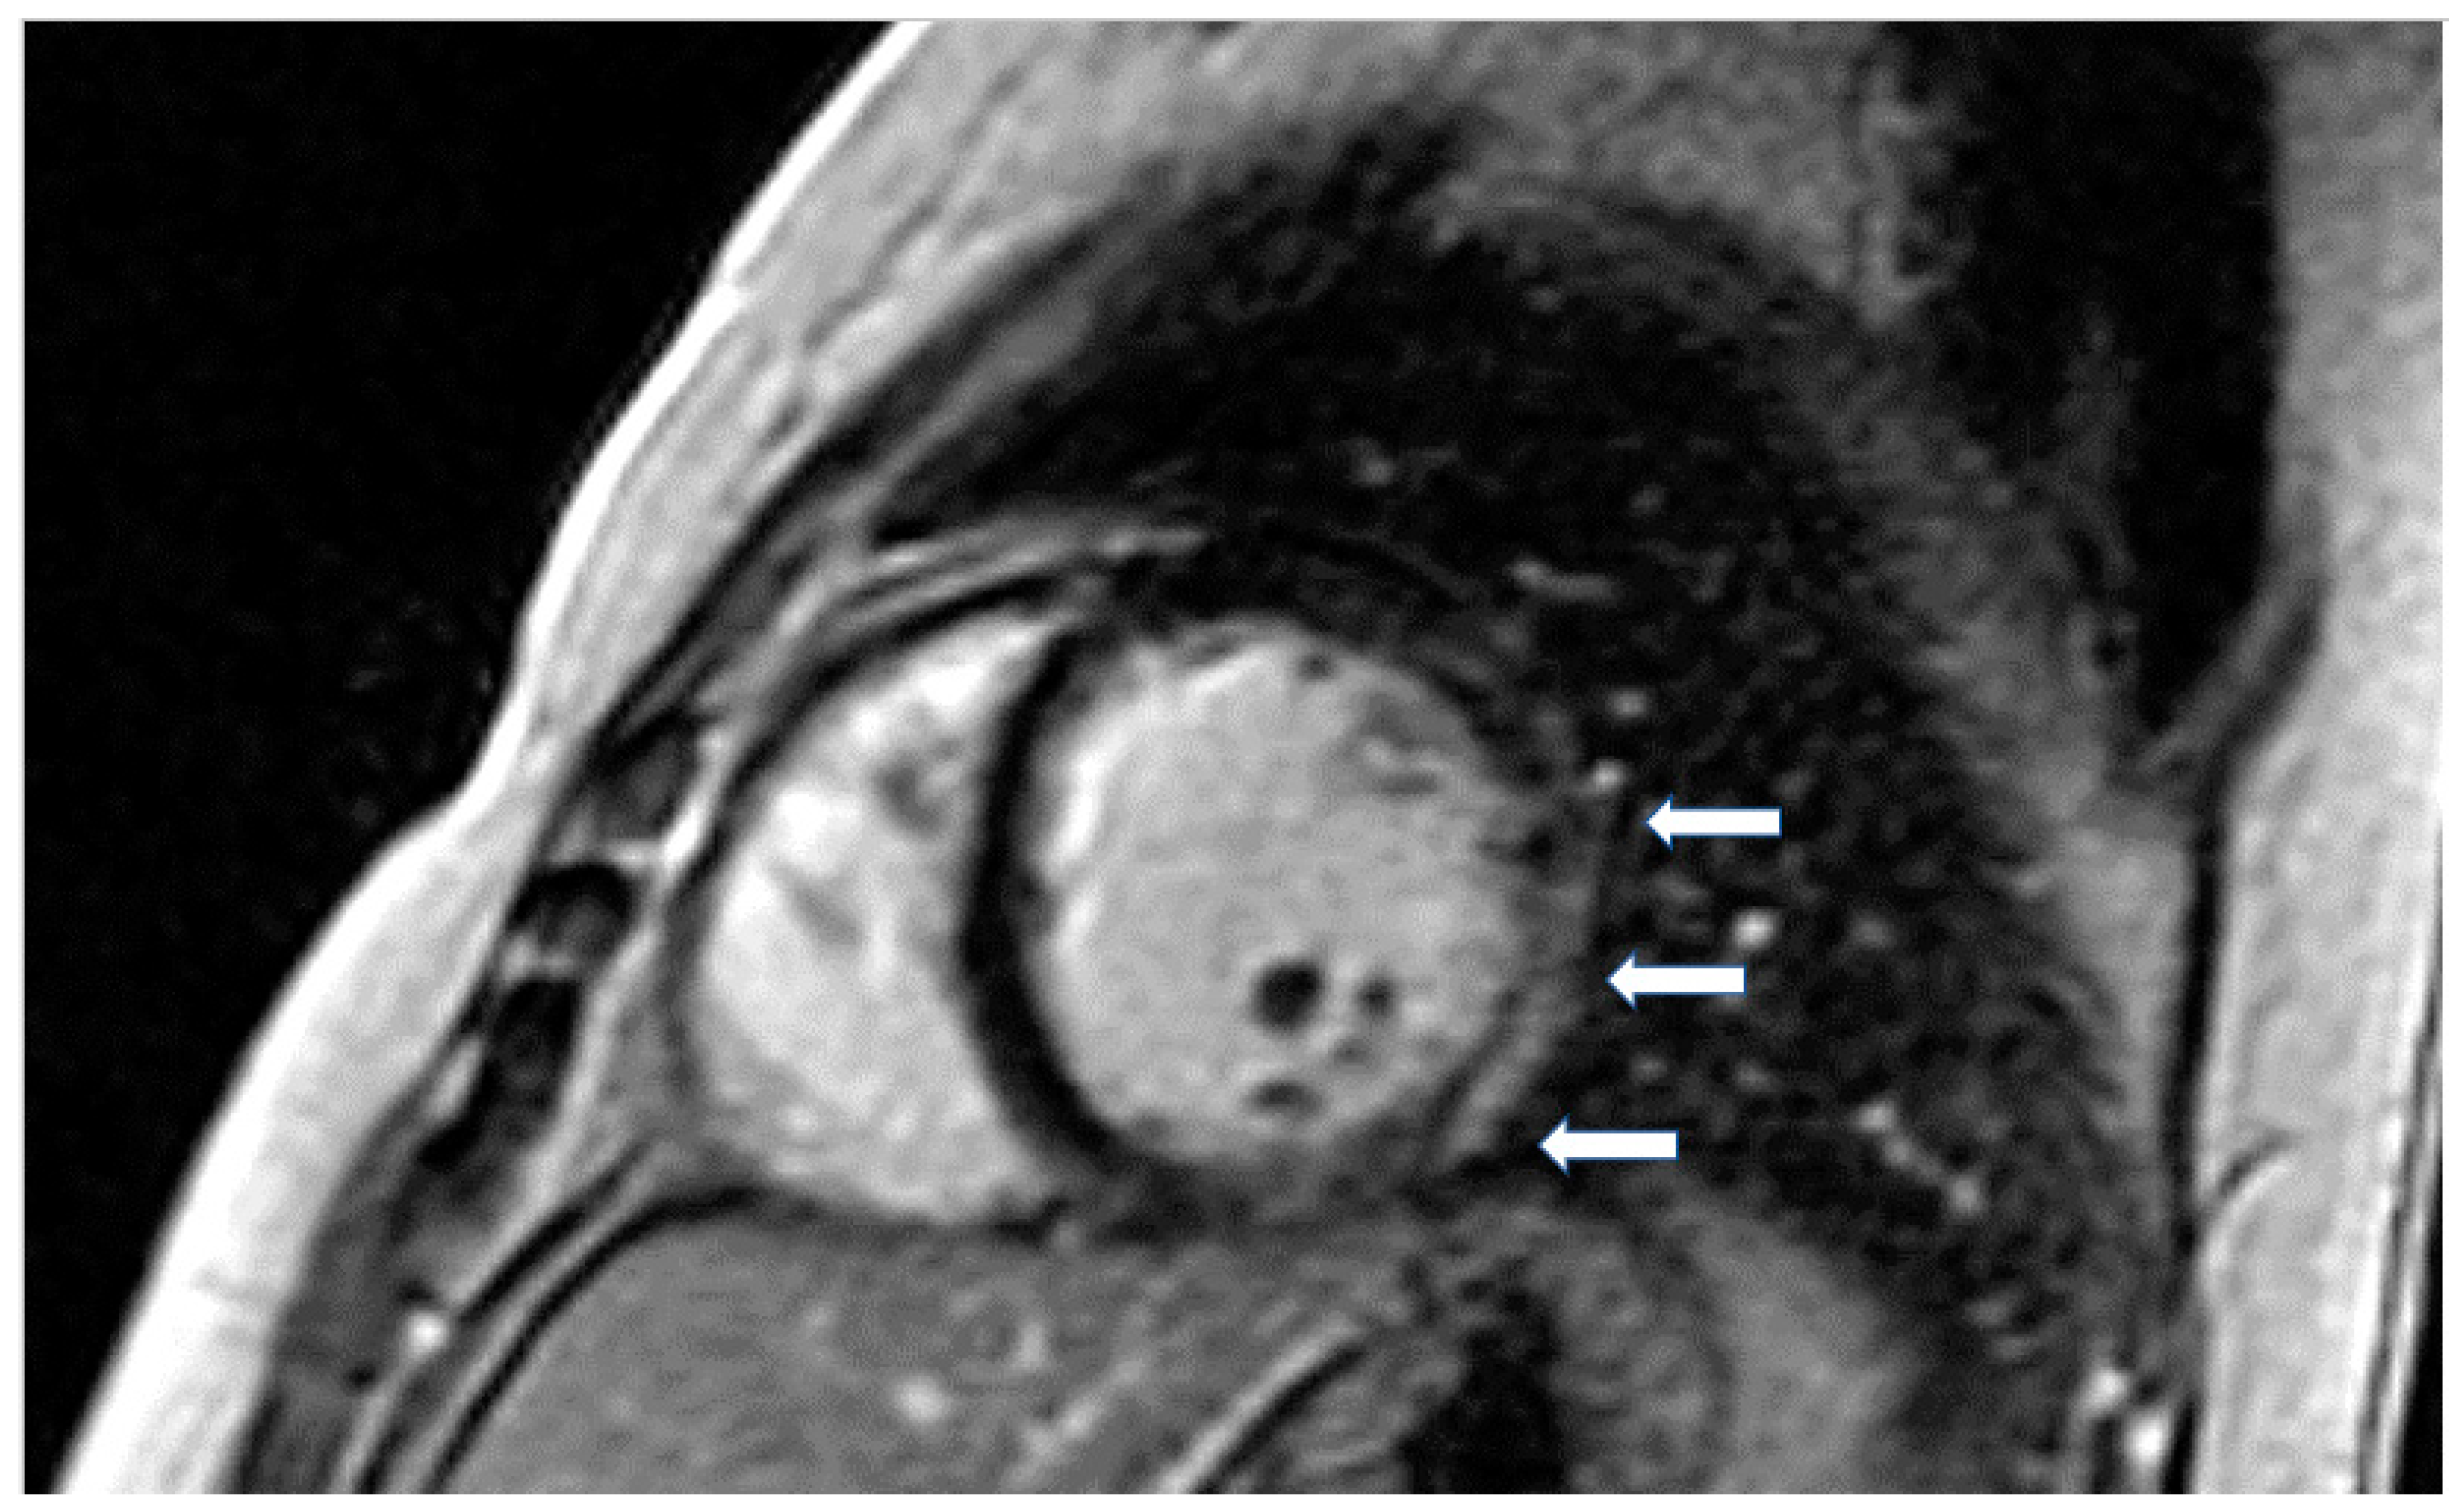

The presence of LGE in HCM, usually in the hypertrophic area, is a high-risk feature, and its presence should be used as a marker for major adverse outcomes such as sudden cardiac death (SCD), arrhythmias, and failure (HF) (Figure 4). It should be also included as an additional index in decision making for implantable cardioverter defibrillators for primary prevention [64]. LGE is usually present in segments with hypertrophy, in some end-stage cases, some segments may appear thinned with transmural fibrosis. The extent of LGE can be quantified either as a sum of the enhanced areas measured in grams or as a proportion of the total left ventricular mass (percentage of LGE). The percentage of fibrosis varies according to the quantification method used. From those methods, the only validated method against necropsy is the semi-automatic 2-standard-deviation technique, which consists of defining LGE as a 2-standard deviation above the mean signal intensity of the distant myocardium and constitutes the preferred quantification method. LGE is rarely observed in mutation carriers without LVH. In a study including patients with pathogenic sarcomere mutations and hypertrophic cardiomyopathy, subjects with mutations but no LV hypertrophy, and controls, CMR showed LGE in 71% of subjects with overt hypertrophy but in none of the mutation carriers without hypertrophy. Different studies have shown an increase in the risk of ventricular arrhythmias in patients with HCM related to the presence of fibrosis evaluated by LGE in comparison with individuals without LGE [63].

Figure 4.

Four chamber inversion recovery image showing severe hypertrophy and extensive LGE (arrows).